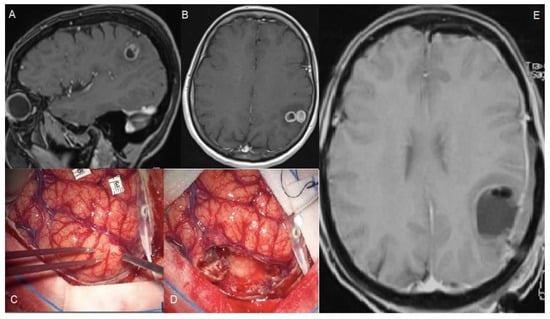

| Esquenazi et al., 2017 | Resection beyond T1c edges | ≈37.5 months more | 35.5 (0.4–107) | 33% Frontal, 42% Temporal, 22% Parietal, an d3% Occipital | NA | Neuronavigation | NA | The subpial technique permitted an SMR with an improved OS, without new deficits |